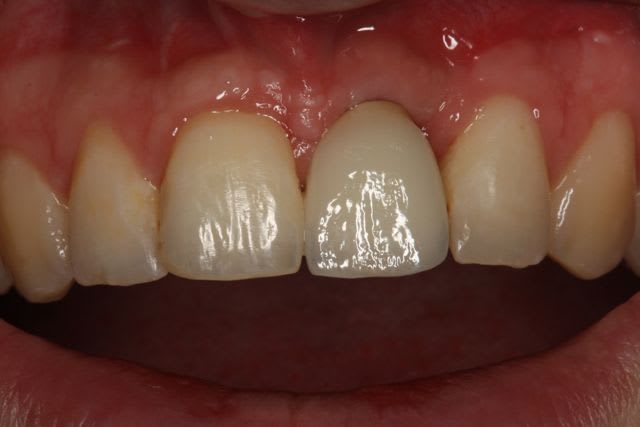

le liseré visible en cervicale n'est pas le pilier mais le petit suintement dut à la sonde pour enlever les excès de ciment

Par contre une petite remarque pourquoi avoir fait une couronne aussi triangulaire? Accentuer le coté rectangulaire aurait permis une formation et un maintien plus facile de la papille distale. De plus cela aurait plus symétrique. Donc plus esthétique.

+1 pour la remarque sur la forme de la couronne

pour la forme de la couronne c'est vrai, je suis 100% d'accord.

Mais comme le patient ne découvre pas, c'est pas trop important pour lui.

Malgré la 'finition au labo' le glaçage est trop marqué, ce qui rend la dent un peu trop brillante par rapport au autre d'ou l'aspect chouilla trop neuf. mais a part nous avec nos yeux trop exigent qui le voit ?